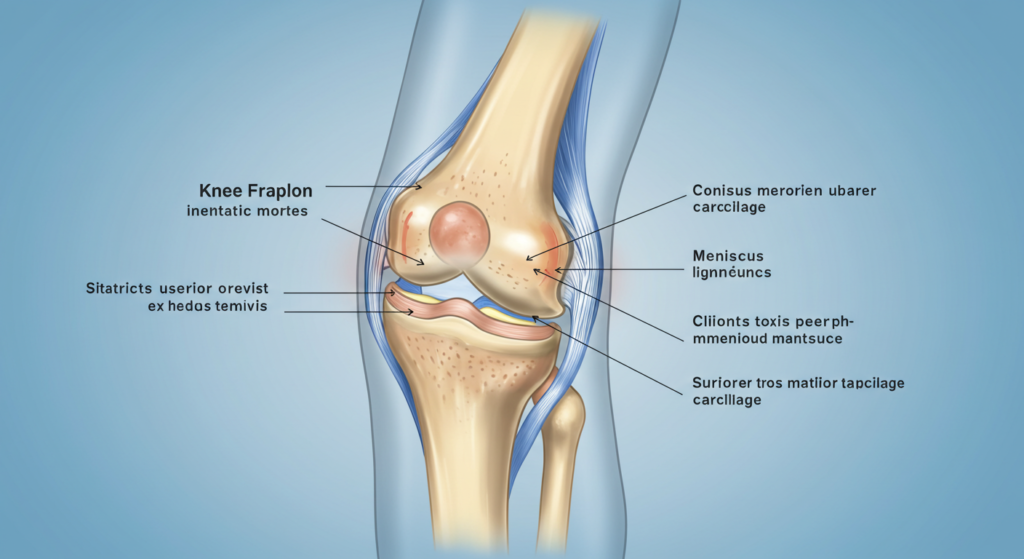

Bunyi “klik” pada lutut boleh berlaku disebabkan oleh pelbagai faktor, termasuk perubahan dalam struktur sendi, geseran antara tulang atau tisu, serta masalah kesihatan tertentu yang berkaitan dengan sakit lutut. Dalam sesetengah kes, bunyi ini tidak mendatangkan sebarang kesan buruk dan boleh dianggap sebagai perkara biasa. Namun, jika bunyi “klik” ini disertai dengan sakit lutut yang berpanjangan, ia boleh menjadi tanda awal kepada masalah yang lebih serius, seperti kecederaan ligamen, osteoartritis, atau keadaan lain yang memerlukan perhatian perubatan.

Bunyi ini boleh berlaku apabila terdapat geseran antara tulang rawan, ligamen, atau tendon yang bergerak di sekitar sendi lutut. Keadaan ini sering berlaku apabila seseorang mengubah kedudukan secara tiba-tiba, seperti daripada duduk ke berdiri atau ketika mencangkung. Contohnya, seorang atlet yang kerap melakukan pergerakan pantas seperti melompat dan mendarat mungkin mengalami geseran tisu ini dengan lebih ketara. Jika geseran ini berterusan, ia boleh menyebabkan sakit lutut akibat tekanan yang dikenakan pada sendi secara berulang kali.

Jika bunyi “klik” disertai dengan sakit lutut, bengkak, atau pergerakan yang terhad, ini boleh menandakan kecederaan yang lebih serius seperti kecederaan ligamen, koyakan meniskus, atau osteoartritis. Sebagai contoh, pemain bola sepak yang mengalami hentakan kuat pada lutut boleh mengalami koyakan meniskus, menyebabkan lutut berbunyi setiap kali bergerak. Keadaan ini bukan sahaja menyebabkan sakit lutut yang berpanjangan, tetapi juga boleh mengganggu keupayaan untuk berjalan dan melakukan aktiviti harian.

Artritis Lutut Osteoartritis adalah satu keadaan degeneratif yang berlaku apabila tulang rawan yang melindungi sendi lutut mula haus akibat penggunaan yang berlebihan atau faktor penuaan. Apabila tulang rawan semakin menipis, pergerakan lutut boleh menghasilkan bunyi “klik” serta menyebabkan sakit lutut kronik. Contohnya, individu berusia 50 tahun ke atas yang sering mengalami kesukaran untuk berjalan jarak jauh atau menaiki tangga mungkin mengalami osteoartritis lutut. Jika keadaan ini tidak dirawat, ia boleh menyebabkan kesakitan yang semakin teruk dan menjejaskan mobiliti. (Sumber: https://www.alodokter.com/osteoarthritis)